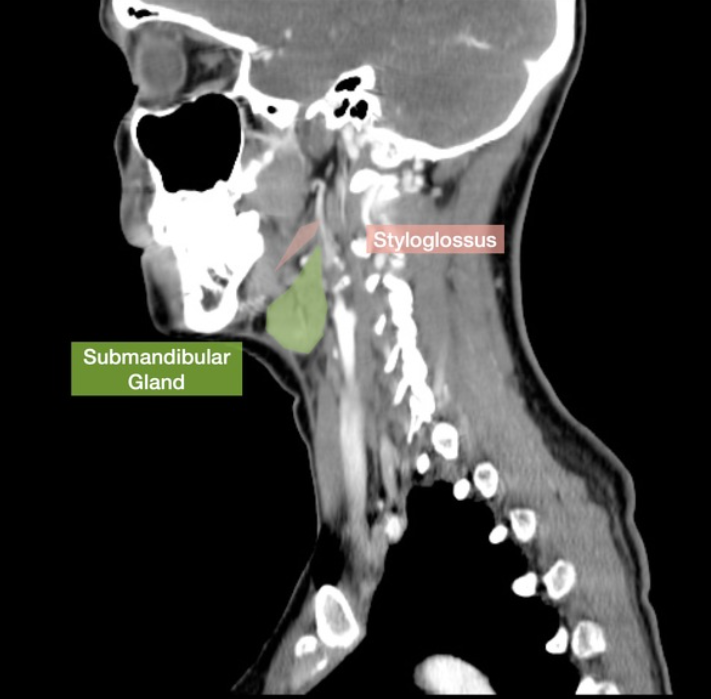

Please label

What gland is this?